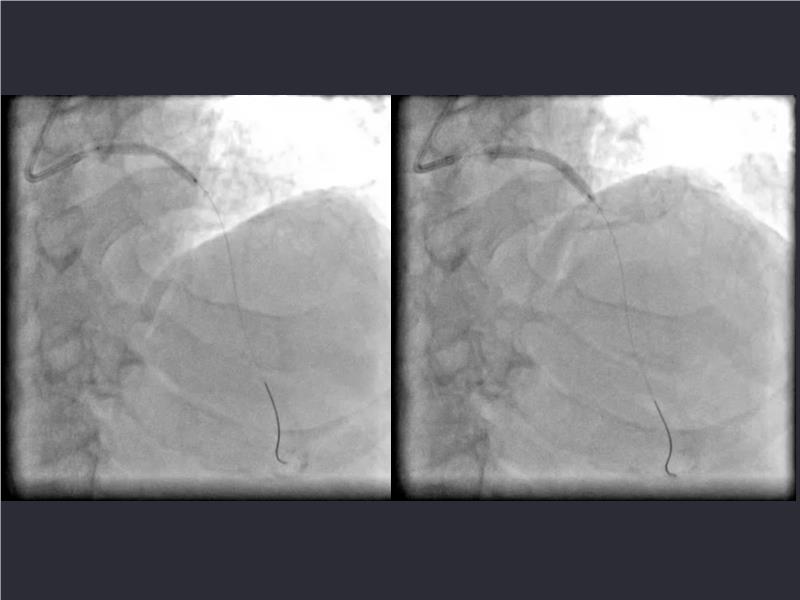

- To understand novel tools and techniques for effective management of bifurcation lesions and long diffused lesions using dedicated stenting solutions